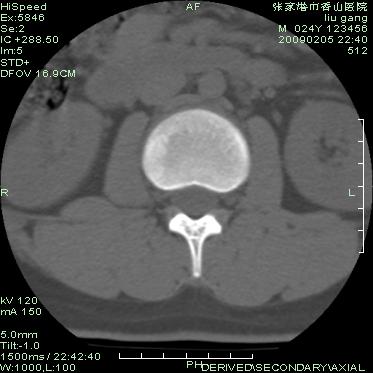

以下是引用随光逐影在2009-3-11 14:43:00的发言:[br]平片:l3、4、5及s1前上缘见类似“切角征”。[br]ct扫描:腰椎多个节段椎间盘向椎体内(椎体前部)突出。